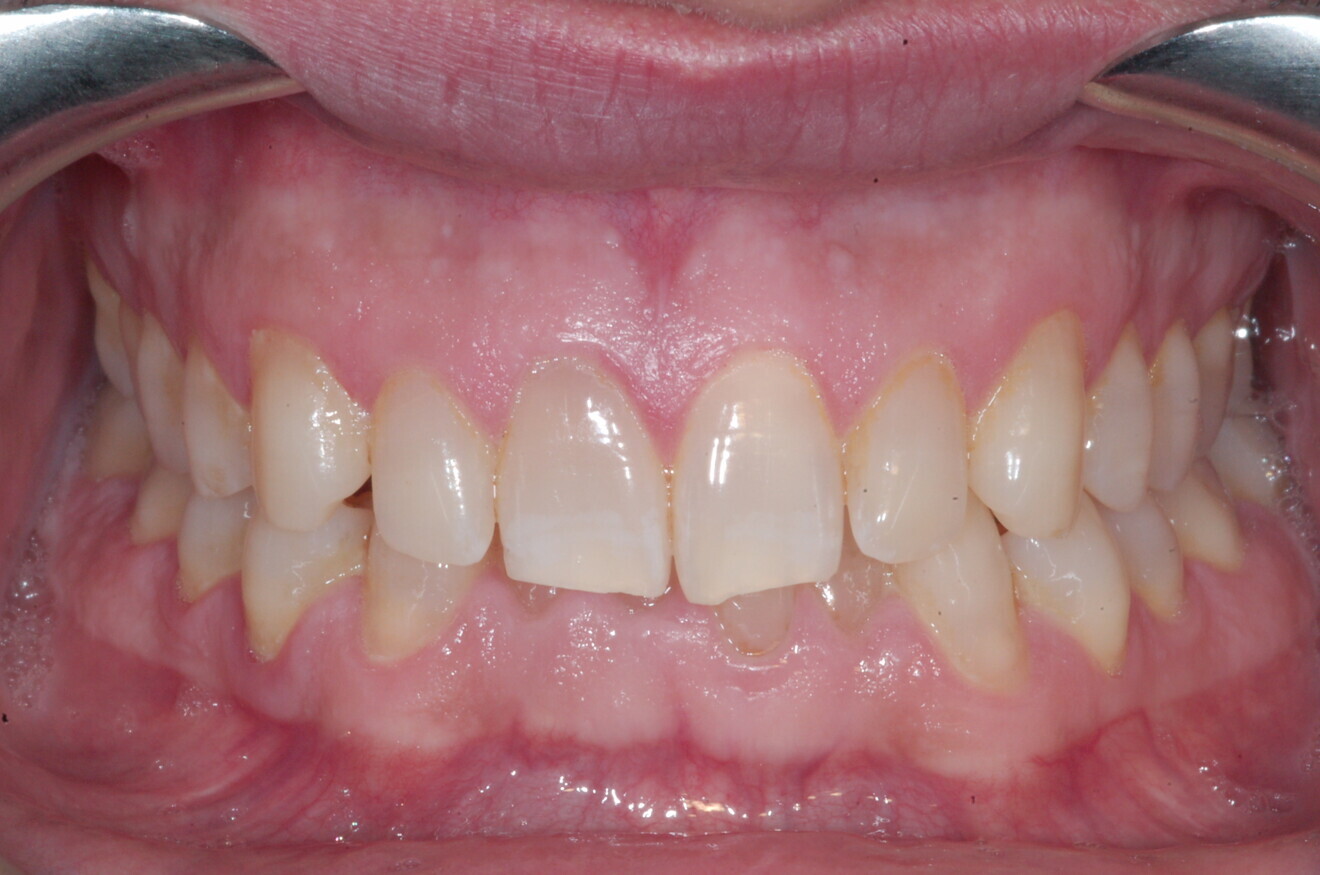

A 37-year-old male patient presented with the chief need for re establishing anterior alignment in both arches. Facial analysis showed a short face with a flat profile but proper chin projection (Figs. 9–12), and clinical examination revealed a skeletal Class I (ANB = 0.89°) and dental Class I malocclusion with severe deep bite (almost 100%), a deep curve of Spee, normal maxillary central incisor torque (Ui–FH = 110°), mild maxillary crowding and moderate mandibular crowding (Figs. 13–18). The deep bite components were represented in this patient by the severe skeletal condition of hypo divergent pattern (FMA = 14.24°) with normal maxillary and mandibular incisor inclination and decreased gonial angle (110.46°). Analysis of the cephalometric radiograph indicated a reduced lower anterior facial height, combined with a hypo-divergent pattern (Fig. 19). The only treatment option suggested was orthodontic treatment with aligners for deep bite correction with all the features described (bite ramps, pressure area, 3D curve of Spee levelling, Class II elastics and heavy occlusal contacts).

The digital treatment plan (ClinCheck) provided 12 aligners for the maxillary arch and 17 for the mandibular arch. The treatment objectives were focused on coupled vertical movements of posterior extrusion and anterior intrusion by means of bite ramps, providing for posterior disocclusion and anterior intrusion of mandibular teeth by means of extrusion attachments needed for mandibular arch levelling. The maxillary and mandibular incisors were proclined to level the upper and lower curve of Spee and to support the flat profile and the lips. Class II elastics were planned to support mandibular proclination and heavy posterior occlusal contacts with relative posterior extrusion. Lateral and posterior maxillary torque were planned to be close to 0°, to achieve wider arch design and ideal intercuspation. No digital over-engineering was planned in the set-up. Because of the age of the patient, the aligners were changed every ten days for a treatment time of less than six months. At the end of the first stage of aligners (Figs. 20–24), an additional stage was planned to improve molar intercuspation without elastics with a digital plan of five further aligners. This brought the total treatment time to 7.5 months since the additional aligners were changed every week.

At the end of the treatment, Class I canine and molar relationships were obtained, maxillary incisor inclination was slightly increased (Ui–FH = 112°), mandibular incisor inclination (IMPA = 97.09°) was fully corrected by means of proclination and the divergency was slightly increased (SN–GoGn = 27°) because of the relative posterior extrusion and use of Class II elastics—a small variation (1°), which is interesting considering the age of the patient (Figs. 25–35). A balanced smile arc was obtained with an ideal relationship between the maxillary incisors and lower lip, and torque control of the lateral and posterior segments generated a broader smile.